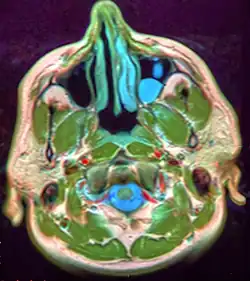

Mucous extravasation phenomenon is a swelling of connective tissue consisting of a collection of fluid called mucus. This occurs because of a ruptured salivary gland duct usually caused by local trauma (damage) in the case of mucous extravasation phenomenon and an obstructed or ruptured salivary duct in the case of a mucus retention cyst. The mucocele has a bluish, translucent color, and is more commonly found in children and young adults.

The size of oral mucoceles vary from 1 mm to several centimeters and they usually are slightly transparent with a blue tinge. On palpation, mucoceles may appear fluctuant, but can also be firm. Their duration lasts from days to years,[4] and may have recurrent swelling with occasional rupturing of its contents.